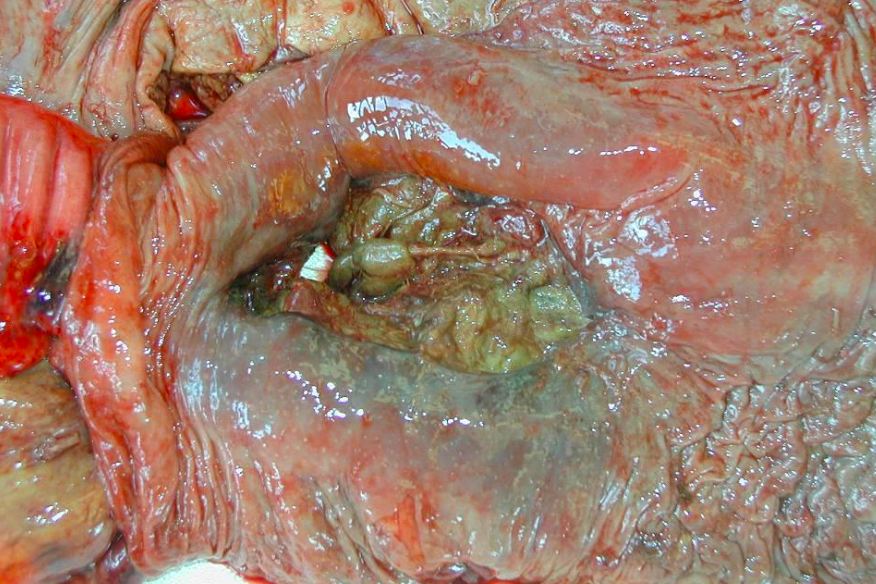

Rupture large intestines - Horse